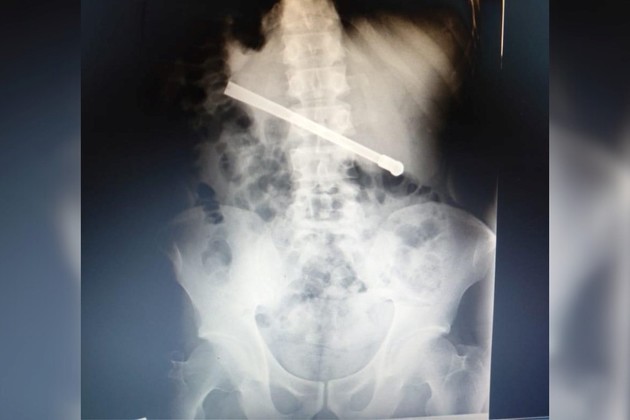

Un preso se tragó una bombilla y terminó en el hospital en Rosario

El interno, alojado en el Pabellón de Aislamiento, sufrió fuertes dolores abdominales y debió ser trasladado a un centro de salud.

El preso, identificado como R.O.F., alojado en la celda N° 06, fue asistido de inmediato por personal penitenciario. Según trascendió, el hombre había ingerido una bombilla metálica, lo que le provocó un severo malestar abdominal.